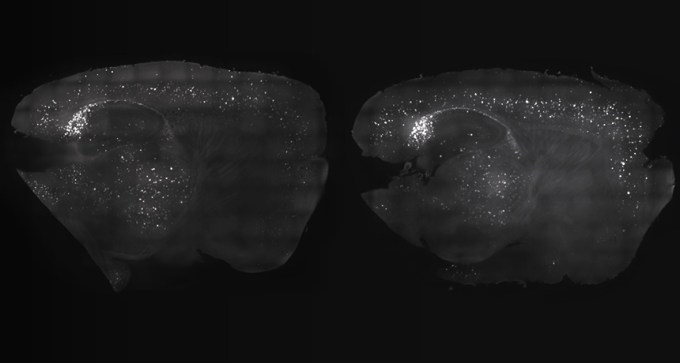

11. Health & Medicine

Flickers and buzzes sweep mouse brains of Alzheimer’s plaques

Precisely timed clicking noises can counter signs of Alzheimer’s in the brains of mice and improve memory.